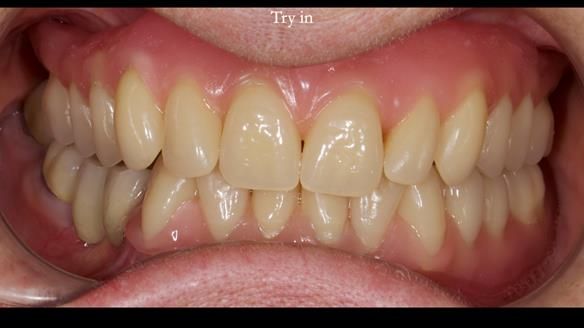

Mary’s upper occlusal plane wasn’t parallel to her interpupillary line, and she specifically wanted that natural asymmetry preserved. Rowan arranged the teeth beautifully, following the exact contour and character of her original smile.

For both the upper and lower dentures, we used Schottlander Enigma Life teeth. I’ve been using these since 2014 and they’ve been outstanding - the surface texture, colour depth, and light reflection are superb. When arranged to mirror the patient’s natural tooth positions, they look completely lifelike.